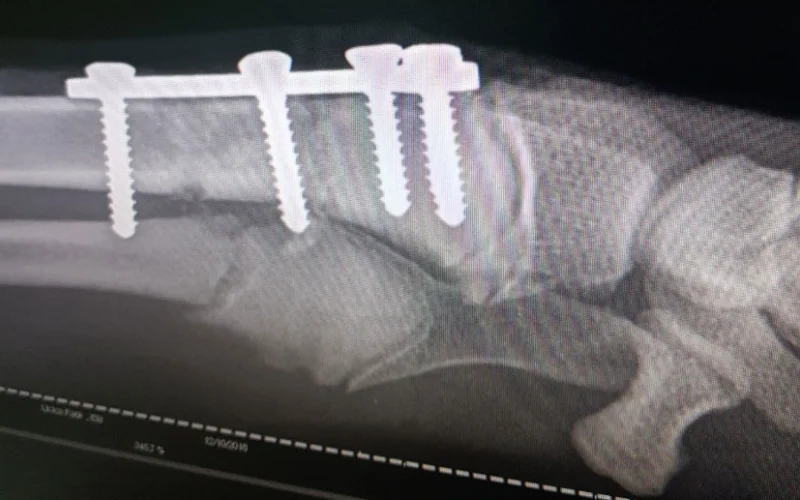

Osim standardnih i uobičajeno prisutnih problema sa frakturama kostiju (lom kosti) ili iščašenjima zglobova (luksacija), posebna stručnost i poznavanje ove oblasti je potrebna za utvrđivanje određenih specifičnih bolesti sistema za kretanje kod pasa i mačaka, koje mogu biti urođene i nasljedne. Sastavni dio ortopedskog pregleda, često neizostavan i u dijagnostičkom smislu je radiološki pregled (rendgenski snimak). Na taj način veterinar dobija preciznije rezultate pretrage, te donosi odgovarajuću odluku o adekvatnoj intervenciji ili liječenju ljubimaca.